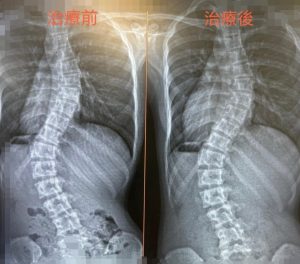

脊椎側彎中醫治療案例

張小友(化名) 2022年因為專注力障礙來診,雖然主要不是主要處理脊椎問題,但每周須針灸背部膀 …